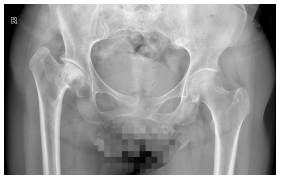

认识“扁平髋”:被压扁的股骨头之痛 “扁平髋”通常指儿童期股骨头缺血性坏死(如Perthes病)愈合后遗留的畸形,也可见于严重的髋臼发育不良或激素性坏死晚期。正常股骨头呈光滑球体,而“扁平髋”患者的股骨头因缺血坏死塌陷,变成“蘑菇状”或“被压扁的圆锥”。这种结构异常导致髋关节“头臼匹配”严重失调,如同不圆的轮子强行在轴承中运转,长期异常摩擦会迅速破坏关节软骨,引发难以忍受的疼痛和跛行(常被误诊为腰椎问题)。药物对此效果有限,人工关节置换是解除病痛、恢复功能的根本途径。

技术亮点:精准置换,稳定耐用 针对“扁平髋”常伴随的股骨头严重变形、髋臼发育不良或异常增生等复杂情况(属于关节置换中的难点),阿坝州人民医院骨科团队精准施术。术中特别选用了带高边设计的高交联聚乙烯/陶瓷摩擦界面。该界面具有极低的磨损率,显著提升了假体的长期稳定性和使用寿命,确保患者术后关节功能得到良好恢复,力线重建满意。